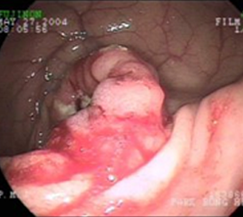

• 대장 내시경

항문을 통하여 내시경을 삽입하여 대장 전체를 관찰하는 검사로 대장 질환을 가장 정확히 진단 할 수 있다. 환자는 검사를 위해서 전날 저녁식사는 죽 등으로 가볍게 하고 하제를 복용하여 대장 내에 남아있는 변을 제거하여야 한다. 대장 내시경검사는 대장암, 대장 용종의 발견에 있어 진단률이 매우 높고 조직검사와 용종 제거가 가능하므로 매우 유용한 검사법이나, 검사하는 동안 통증을 느낄 수 있고, 통증을 줄이기 위해 수면유도제를 사용할 경우 약물사용으로 인한 부작용이 나타날 수 있다. 또한 드물긴 하지만 장 천공 등의 합병증이 생길 수 있으며 암 등으로 대장이 막혀 있으면 더 이상 검사를 진행할 수 없는 단점이 있다.

대장내시경검사에서 확인된 대장암 대장내시경검사에서 확인된 대장 이미지